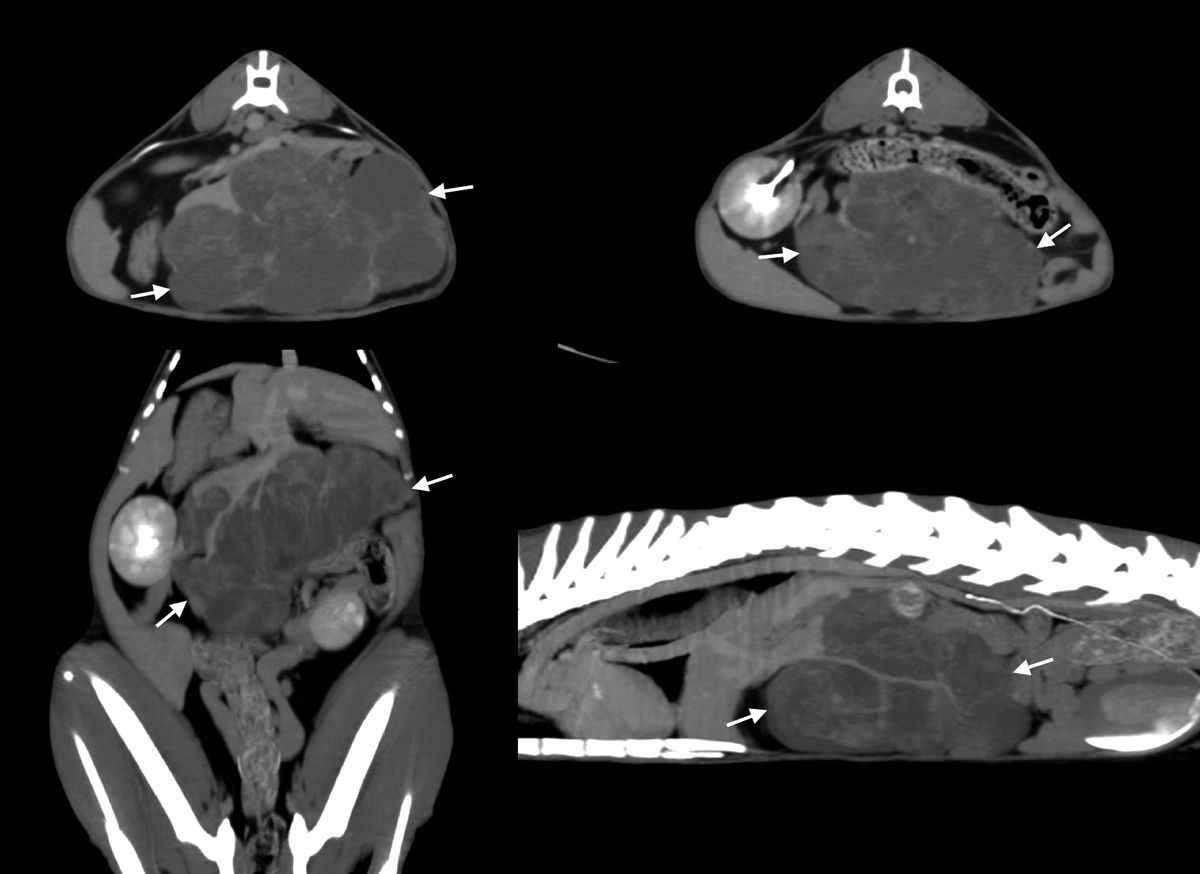

Immagini TC di un tumore epatico in un gatto. Immagini trasversali (sopra) e immagini dorsale e sagittale riformattate nella proiezione di massima intensità (sotto). Al centro del fegato può essere osservata questa grande massa, con contorni chiaramente delineati, che aiuta a pianificare la rimozione chirurgica.

Figura 5. Immagini TC di un tumore epatico in un gatto. Immagini trasversali (sopra) e immagini dorsale e sagittale riformattate nella proiezione di massima intensità (sotto). Al centro del fegato può essere osservata questa grande massa, con contorni chiaramente delineati, che aiuta a pianificare la rimozione chirurgica.© Laurent Blond

L'imaging tramite TC richiede il paziente in anestesia generale e l’uso di mezzo di contrasto iodato iniettato per via endovenosa. È molto utile per esaminare l'intero fegato, specialmente nei cani di taglia grande dove l'ecografia può avere dei limiti. Il cane può essere posizionato in decubito dorsale o ventrale, e le immagini acquisite sul piano trasversale possono essere riformattate su piani diversi. Il fegato di norma mostra l'attenuazione omogenea dei tessuti molli. La TC è specificamente raccomandata per valutare l'esatta posizione di una massa epatica e la sua possibile disseminazione in vista di una chirurgia (Figura 5). Inoltre, è molto utile per valutare le anomalie vascolari, soprattutto gli shunt portosistemici (intraepatici o extraepatici); in questo caso, dopo l'iniezione del mezzo di contrasto, sono necessari tre tempi di acquisizione: fase arteriosa, fase portale e fase venosa [2].